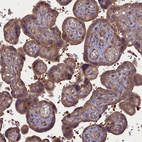

Immunohistochemical staining of human kidney shows strong cytoplasmic positivity in cells in tubules.